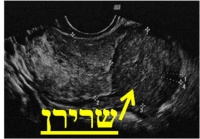

בדיקת האולטרה-סאונד היא בדיקה זמינה ופשוטה. הבדיקה מאפשרת לקבל פרטים על מבנה וגודל הרחם, מיקום וגודל השרירנים, רירית הרחם, אספקת הדם, מראה השחלות, ועוד. אם וכאשר מודגמים שרירנים על מסך הסריקה, מקובל לתעד זאת ולמדוד את גודלם. התמונות מודפסות ישירות ממסך המכשיר. ניתן לראות בהן צללים המייצגים שרירנים, וסמני מחשב המגדירים את מידותיהם.

מיומה2א.JPG מיומה2ב.JPG מיומה2ג.JPG

תרשים מספר 2: תמונות מבדיקות אולטרה-סאונד המדגימות שרירני רחם

במרבית המקרים, לא ניתן לקבל החלטות טיפוליות על סמך תמונות האולטרה-סאונד בלבד. יש לבצע תיעוד נלווה של הממצא במילים ובאיור, המתאר את מספר השרירנים וגודלם ואת מיקומם ביחס לדופן הרחם, ולסכם את תוצאות הבדיקה בצורה מדויקת. הסיכום, הנעשה על ידי הרופא המבצע, משמש לקבלת ההחלטה אודות הטיפול המתאים ביותר לצורך ולרצון האשה.